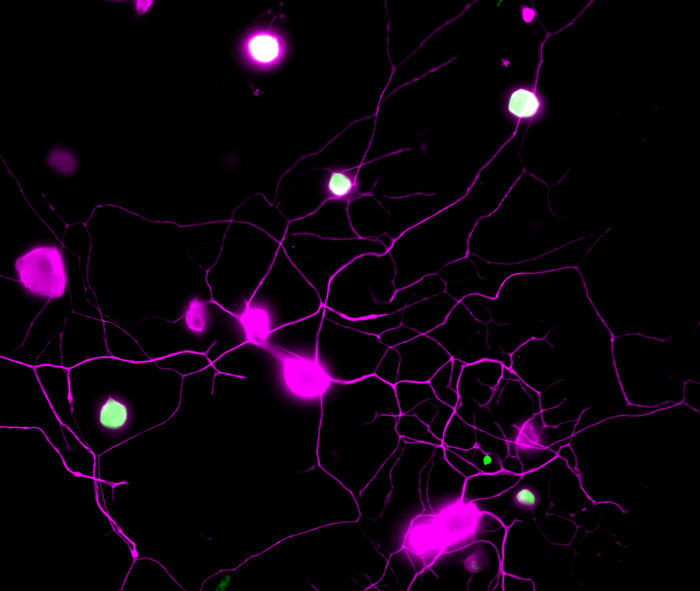

Η ερευνητική ομάδα είχε ανακαλύψει προηγουμένως ότι οι αισθητικοί νευρώνες παράγουν έναν μεταβολίτη που ονομάζεται BH4 και ο οποίος μπορεί να προκαλέσει χρόνιο πόνο. Υψηλότερες συγκεντρώσεις του BH4 έχουν συνδεθεί με αυξημένη ευαισθησία και επίμονο πόνο. Με βάση αυτά τα ευρήματα, η ομάδα αποφάσισε να ξεκινήσει τη νέα της έρευνα στοχεύοντας το μονοπάτι BH4.

Ο αποκλεισμός της σηματοδότησης EGFR/KRAS μείωσε την ευαισθησία στον πόνο μειώνοντας τα επίπεδα BH4, σύμφωνα με τα νέα ευρήματα. Η σηματοδότηση EGFR/KRAS αύξησε επίσης την έκφραση του GCH1, ενός σημαντικού ενζύμου στην οδό BH4 που συμβάλλει στον νευροπαθητικό πόνο. Έτσι, αποδείχθηκε επίσης ότι ο αποκλεισμός του EGFR ανέστειλε το GCH1 και συνδέθηκε με την ανακούφιση από τον πόνο.

Το GCH1/BH4 δρα συνεργικά με το KRAS για να καθοδηγήσει τον καρκίνο του πνεύμονα και λειτουργεί σαν κοινή οδός σηματοδότησης του χρόνιου πόνου και του καρκίνου του πνεύμονα, αλλά και ως φαρμακευτικός στόχος. Όμως πολλά δεδομένα για τη ρύθμιση της έκφρασης του GCH1 παραμένουν άγνωστα σε ότι αφορά τον τραυματισμό νεύρων ή τη δυνατότητα χρήσης του ως αναλγητικό.